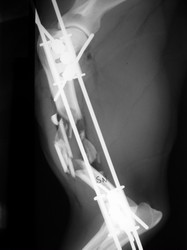

Fijación Externa

Fijación externa en IVOT

PRÁCTICAS CURSO DE FIJACIÓN EXTERNA PERFECCIONAMIENTO.

Húmero.